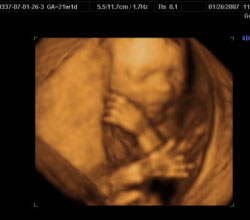

Sin embargo, cuando la ecografía se realiza en un departamento de ginecología, su función es verificar la posición, la salud y otros aspectos del bebé. Además, la tecnología 2D se utiliza para proporcionar dos dimensiones de la imagen. Si bien se usa el uso de la tecnología 3D, revela las mismas imágenes en 3 dimensiones que son más claras y prominentes que las 2D. Además, la tecnología 4D lo deja más claro que todo. Además, hace que los pacientes puedan ver las imágenes en movimiento. Incluso, en etapas posteriores de su embarazo, pueden ver los movimientos de su hijo, como sonreír y bostezar. La técnica ultrasónica también ayuda a evaluar si el niño está pasando por algún tipo de anormalidad y se hace la planificación para tratarla.

Las ecografías 2D, 3D y 4D de ginecología se realizan para evaluar el estado y la posición del bebé. Un ultrasonido 4D muestra un video en vivo de los movimientos del bebé dentro del útero. Entonces, muestra al bebé abriendo y cerrando los ojos y chupándose el dedo, etc.

Tanto los ultrasonidos 3D como los 4D pueden proporcionar imágenes tridimensionales del bebé. Si bien una ecografía 4D es esencialmente una ecografía 3D en movimiento en vivo, proporciona información más detallada sobre el bebé. Puede ayudar a diagnosticar varias diferencias congénitas.

Todos los ultrasonidos 2D, 3D y 4D de ginecología brindan una visión del bebé y detectan cualquier problema con él / ella. Sin embargo, un ultrasonido 4D es el más avanzado que muestra un video tridimensional en vivo del bebé. Permite la evaluación en tiempo real de la cara del bebé.